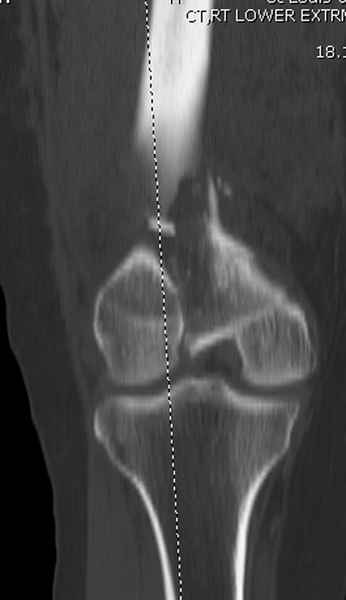

При наличии различных имплантов, любые варианты: слева (полу) открытым - мининвазивным, а справа закрытым интрамедуллярным методом, его считаем более чем приемлемым для фиксации данных переломов.

Проксимальная и дистальная блокировка, независимо от техники введения штифта, ретроградно или антеградно, гарантирует сращение сегментарных переломов бедра без укорочения. Штифты диаметром 12 мм с блокировкой сверху и вниз двумя шурупами выдерживают вес 75 кг больного, что позволяет раннюю профилактику контрактур.

Погоня за "красивой рентгенограммой" не всегда оправдана для фиксации кости, где имеется массивное мягкотканое покрытие. Если так уж хочется исправить положение кости, то при наличии ЭОП, большие костные фрагменты могут быть развернуты или приближены к основному фрагменту методом применения Joystick.

Главное в лечении сегментарных переломов - необходима осторожность при рассверливании канала, продвижение гибкого сверло через сегмент проводят без сверления, толканием, а то были случаи, когда весь сегмент крутился вместе со сверлом.

Из-за вариабельности установки дистальных шурупов и возможности перкутанного введения проксимально предпочитаем DePuy Polyax, хотя на сегодняшнем маркете множеств вариантов фиксации дистального бедра перкутанном методом.